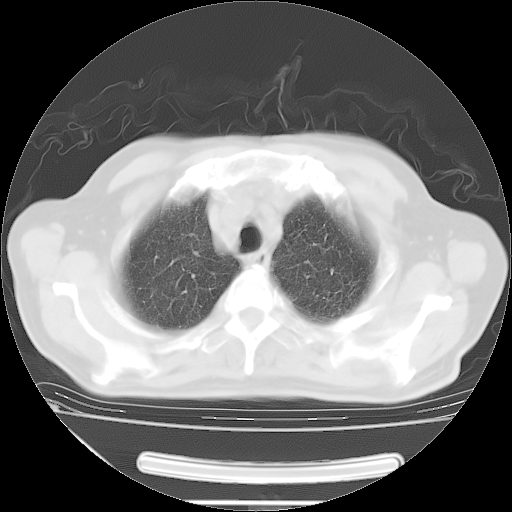

今天复查肺部CT,发现双肺广泛磨玻璃样改变。所以我把3月19日和5月9日相隔50天的肺部CT上传。请大家会诊。

2009年3月19日肺部CT片。

2009年3月19日肺部CT